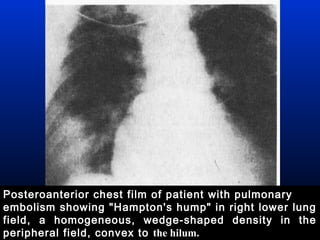

● Hampton’s hump ( a pleural-based,

wedge-shaped infiltrate )

Posteroanterior chest film of patient with pulmonary

embolism showing "Hampton's hump" in right lower lung

field, a homogeneous, wedge-shaped density in the

peripheral field, convex to the hilum.